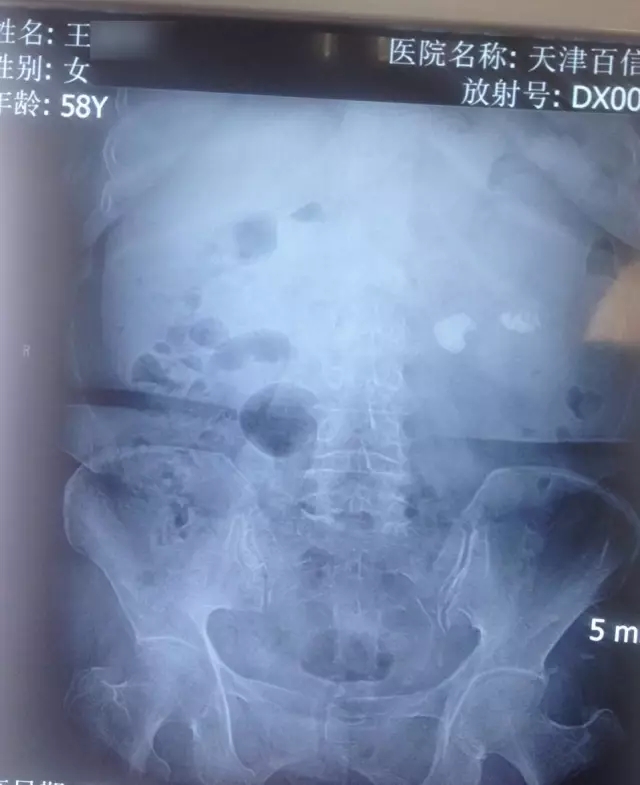

姓名:王女士

年龄:58岁

病症表现:患肾结石10年,腹部剧烈疼痛、血尿

诊断结果:左肾结石

手术方案:经皮肾镜碎石取石术

其他描述:患者患肾结石10年,曾多次体外碎石,效果不理想,反作。入院检查显示,患者左肾布满大小不一的结石,而且大的直径约1.7厘米位于左肾肾盂输尿管移行处。李月明主任为患者进行经皮肾镜碎石取石术,取出患者左肾内结石,术后检查显示,,接触患者10年困扰。